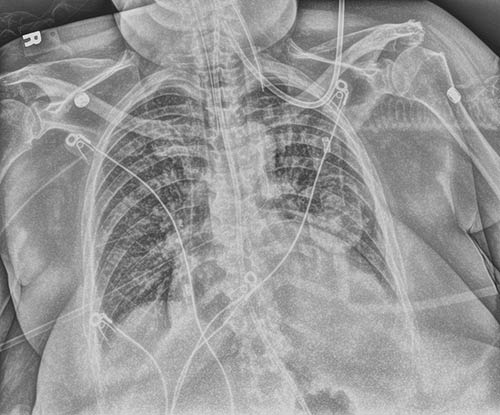

确保一次曝光。球管和插管增强创建相配影像,并采用优化的处理,以便更清晰、更轻松地可视化外周穿刺中心静脉插管和球管。它增强了正确置放球管和插管并保持在原位的信心。